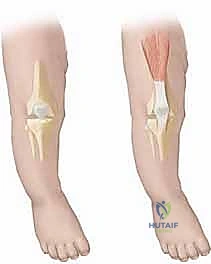

لا يقتصر الأمر في هذه الحالة على مجرد فرط في بسط الركبة (Hyperextension)، بل يمتد ليشمل تقلصاً شديداً في العضلة الرباعية الأمامية للفخذ (Quadriceps)، وتيبساً في كبسولة المفصل، وفي الحالات المتقدمة، انزياحاً كاملاً لعظمة القصبة (Tibia) أمام عظمة الفخذ (Femur). يتطلب هذا التعقيد التشريحي فهماً ميكانيكياً دقيقاً وتعاملاً لطيفاً وحازماً في نفس الوقت لضمان عدم الإضرار بغضاريف النمو الحساسة لدى الرضيع.

لفهم طبيعة خلع الركبة الخلقي، يجب أن ننظر إلى التشريح الدقيق لمفصل الركبة. في الحالة الطبيعية، تعمل الركبة كمفصل رزي (Hinge Joint) يسمح بالانثناء للخلف (Flexion) والبسط للأمام (Extension) حتى زاوية مستقيمة (180 درجة).

في حالة خلع الركبة الخلقي، يحدث خلل في التوازن العضلي والتشريحي:

* العضلة الرباعية (Quadriceps): تصبح هذه العضلة الأمامية قصيرة جداً ومتقلصة بشكل ليفي، مما يسحب عظمة الساق (القصبة) بقوة إلى الأمام والأعلى.

* الأربطة الصليبية والجانبية: قد تعاني من التراخي أو التوتر غير الطبيعي بناءً على درجة الخلع.

* الكبسولة المفصلية: تتقلص الكبسولة الأمامية وتتليف، مما يمنع الركبة من الانثناء للخلف.

* عظمة الرضفة (الصابونة): غالباً ما تكون صغيرة جداً أو غير مكتملة النمو في الأشهر الأولى، وتكون مسحوبة للأعلى وللخارج.